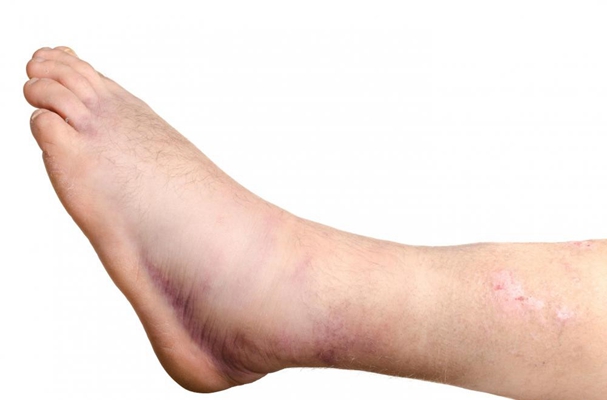

骨癌圖片

骨癌